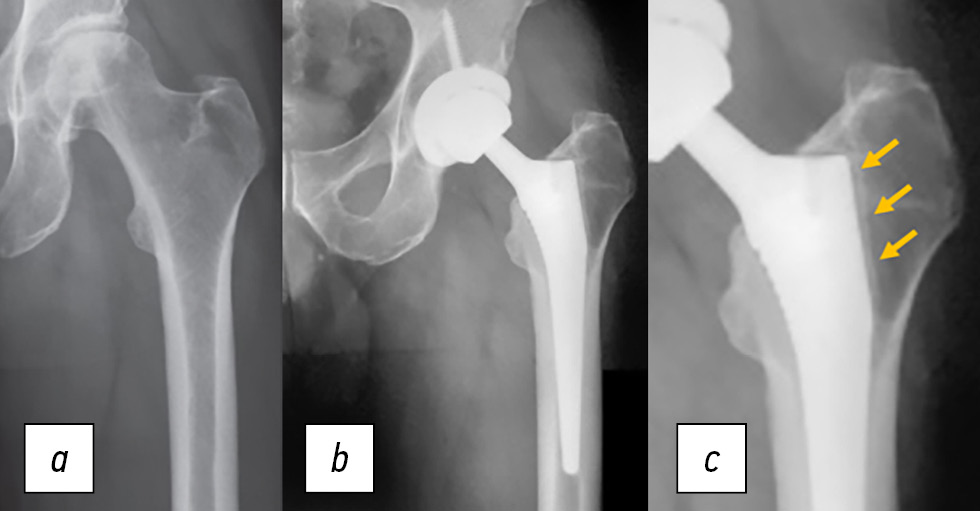

Что касается периимплантного остеолиза, то его частота в группе ОГБК составила 5,8% и была вдвое ниже (2,5%) среди пациентов с ОА. У всех пациентов с данным осложнением зона остеолиза была обнаружена вокруг бедренного компонента эндопротеза. Этот факт, вероятно, обусловлен нарушением кровоснабжения проксимального отдела бедренной кости вследствие остеонекроза головки бедренной кости [25]. Важно отметить, что эти осложнения были диагностированы только рентгенологически и не сопровождались клиническими проявлениями (рис. 1).

Рис. 1. a — рентгенограмма пациента 39 лет с остеонекрозом головки бедренной кости III ст. b — рентгенограмма через 30 мес после тотального эндопротезирования тазобедренного сустава. c — стрелка указывает на зону остеолизиса вокруг проксимального отдела ножки эндопротеза.

Fig. 1. a — radiograph of a 39-year-old patient with grade III osteonecrosis of the femoral head. b — radiograph 30 months after total hip arthroplasty. c — the arrow indicates the zone of osteolysis around the proximal endoprosthesis stem.